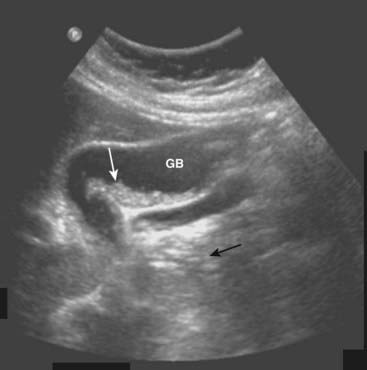

image Gallstones usually fall to the most dependent part of gallbladder, which will depend on the patient’s position at the time of the scan. This helps to differentiate gallstones from polyps or tumors, which may be attached to a nondependent surface. Gallstones are characteristically echogenic and produce acoustical shadowing because they reflect most of the signal (Fig. 19-2).

imageAcoustical shadowing describes a band of reduced echoes behind an echo-dense object (e.g., a gallstone) that reflects most, but not all, of the sound waves. While acoustical shadowing reduces the diagnostic effectiveness of ultrasound through such tissues as bone and bowel gas, its presence can have diagnostic value in identifying the presence of calculi, such as in the gallbladder and kidney (Fig. 19-3).

image

Figure 19-3 Acoustical shadowing.

There is a band of reduced echoes (solid white arrow) behind echogenic gallstones (dotted white arrows) that reflect most, but not all, of the sound waves. The presence of acoustical shadowing can have diagnostic value in identifying the presence of calculi in the gallbladder (GB).

imageBiliary sludge can be found in the lumen of the gallbladder and is an aggregation that may contain cholesterol crystals, bilirubin, and glycoproteins. It is often associated with biliary stasis. While it may be echogenic, sludge does not produce acoustical shadowing like gallstones (Fig. 19-4).

Figure 19-4 Sludge in the gallbladder.

Sludge (solid white arrow) in the gallbladder (GB) is associated with biliary stasis. While it may be echogenic, sludge does not produce acoustical shadowing like gallstones (the absence of shadowing is shown by solid black arrow).